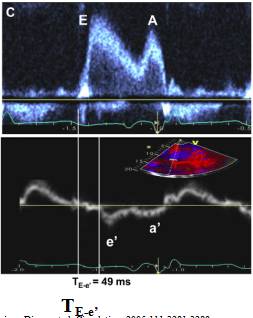

15、二尖瓣血流E波与二尖瓣环e’波开始时间差值TE-e’

16、左房增大—左房容积指数(LAVI)

LAVI(ml/㎡):

●正常值范围:≤28ml/㎡

●轻度受损:29-33ml/㎡

●中度受损:34-39ml/㎡

●重度受损:≥40ml/㎡